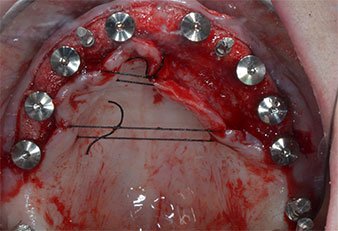

Tre anni dopo era il momento di una protesi dentaria mascellare dello stesso tipo. In base alla pianificazione con CBCT, il rialzo del seno mascellare è stato evitato con l'ausilio di impianti corti e una dima chirurgica è stata utilizzata per trasferire le posizioni pianificate alla cresta alveolare (Figg. 1 e 2).

A causa dell'osso relativamente duro (D2) in quest'area, le sedi dell'impianto di 10 mm nelle posizioni 11 e 21 sono state finalizzate con un trapano rotante da 4 mm di diametro, in combinazione con un contrangolo chirurgico W&H WS-75 L, il motore per impianto W&H Implantmed e il modulo opzionale Osstell ISQ di W&H. Al contrario, a causa dell'osso morbido, le sedi posteriori sono state preparate a un diametro finale di 3 mm utilizzando lo strumento Piezomed I3P. Gli impianti sono stati infine posti per via transgengivale sull'osteointegrato per tre mesi (Figg. 6-10). La protesi dentaria esistente è stata mantenuta su quattro impianti provvisori (Fig. 8).